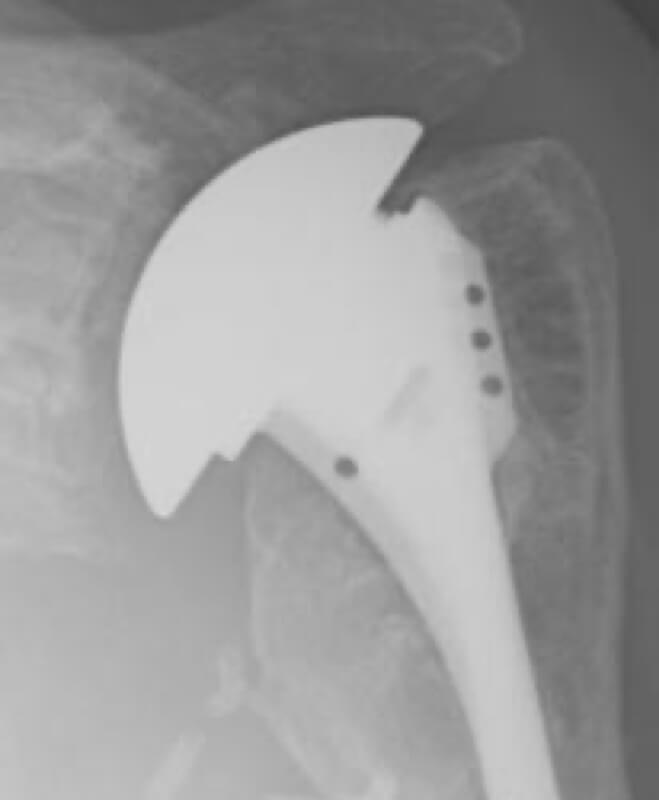

DePuy, Global Advantage